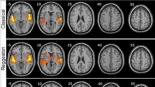

El estudio que afirma que el reggaeton provoca más actividad cerebral que la música clásica